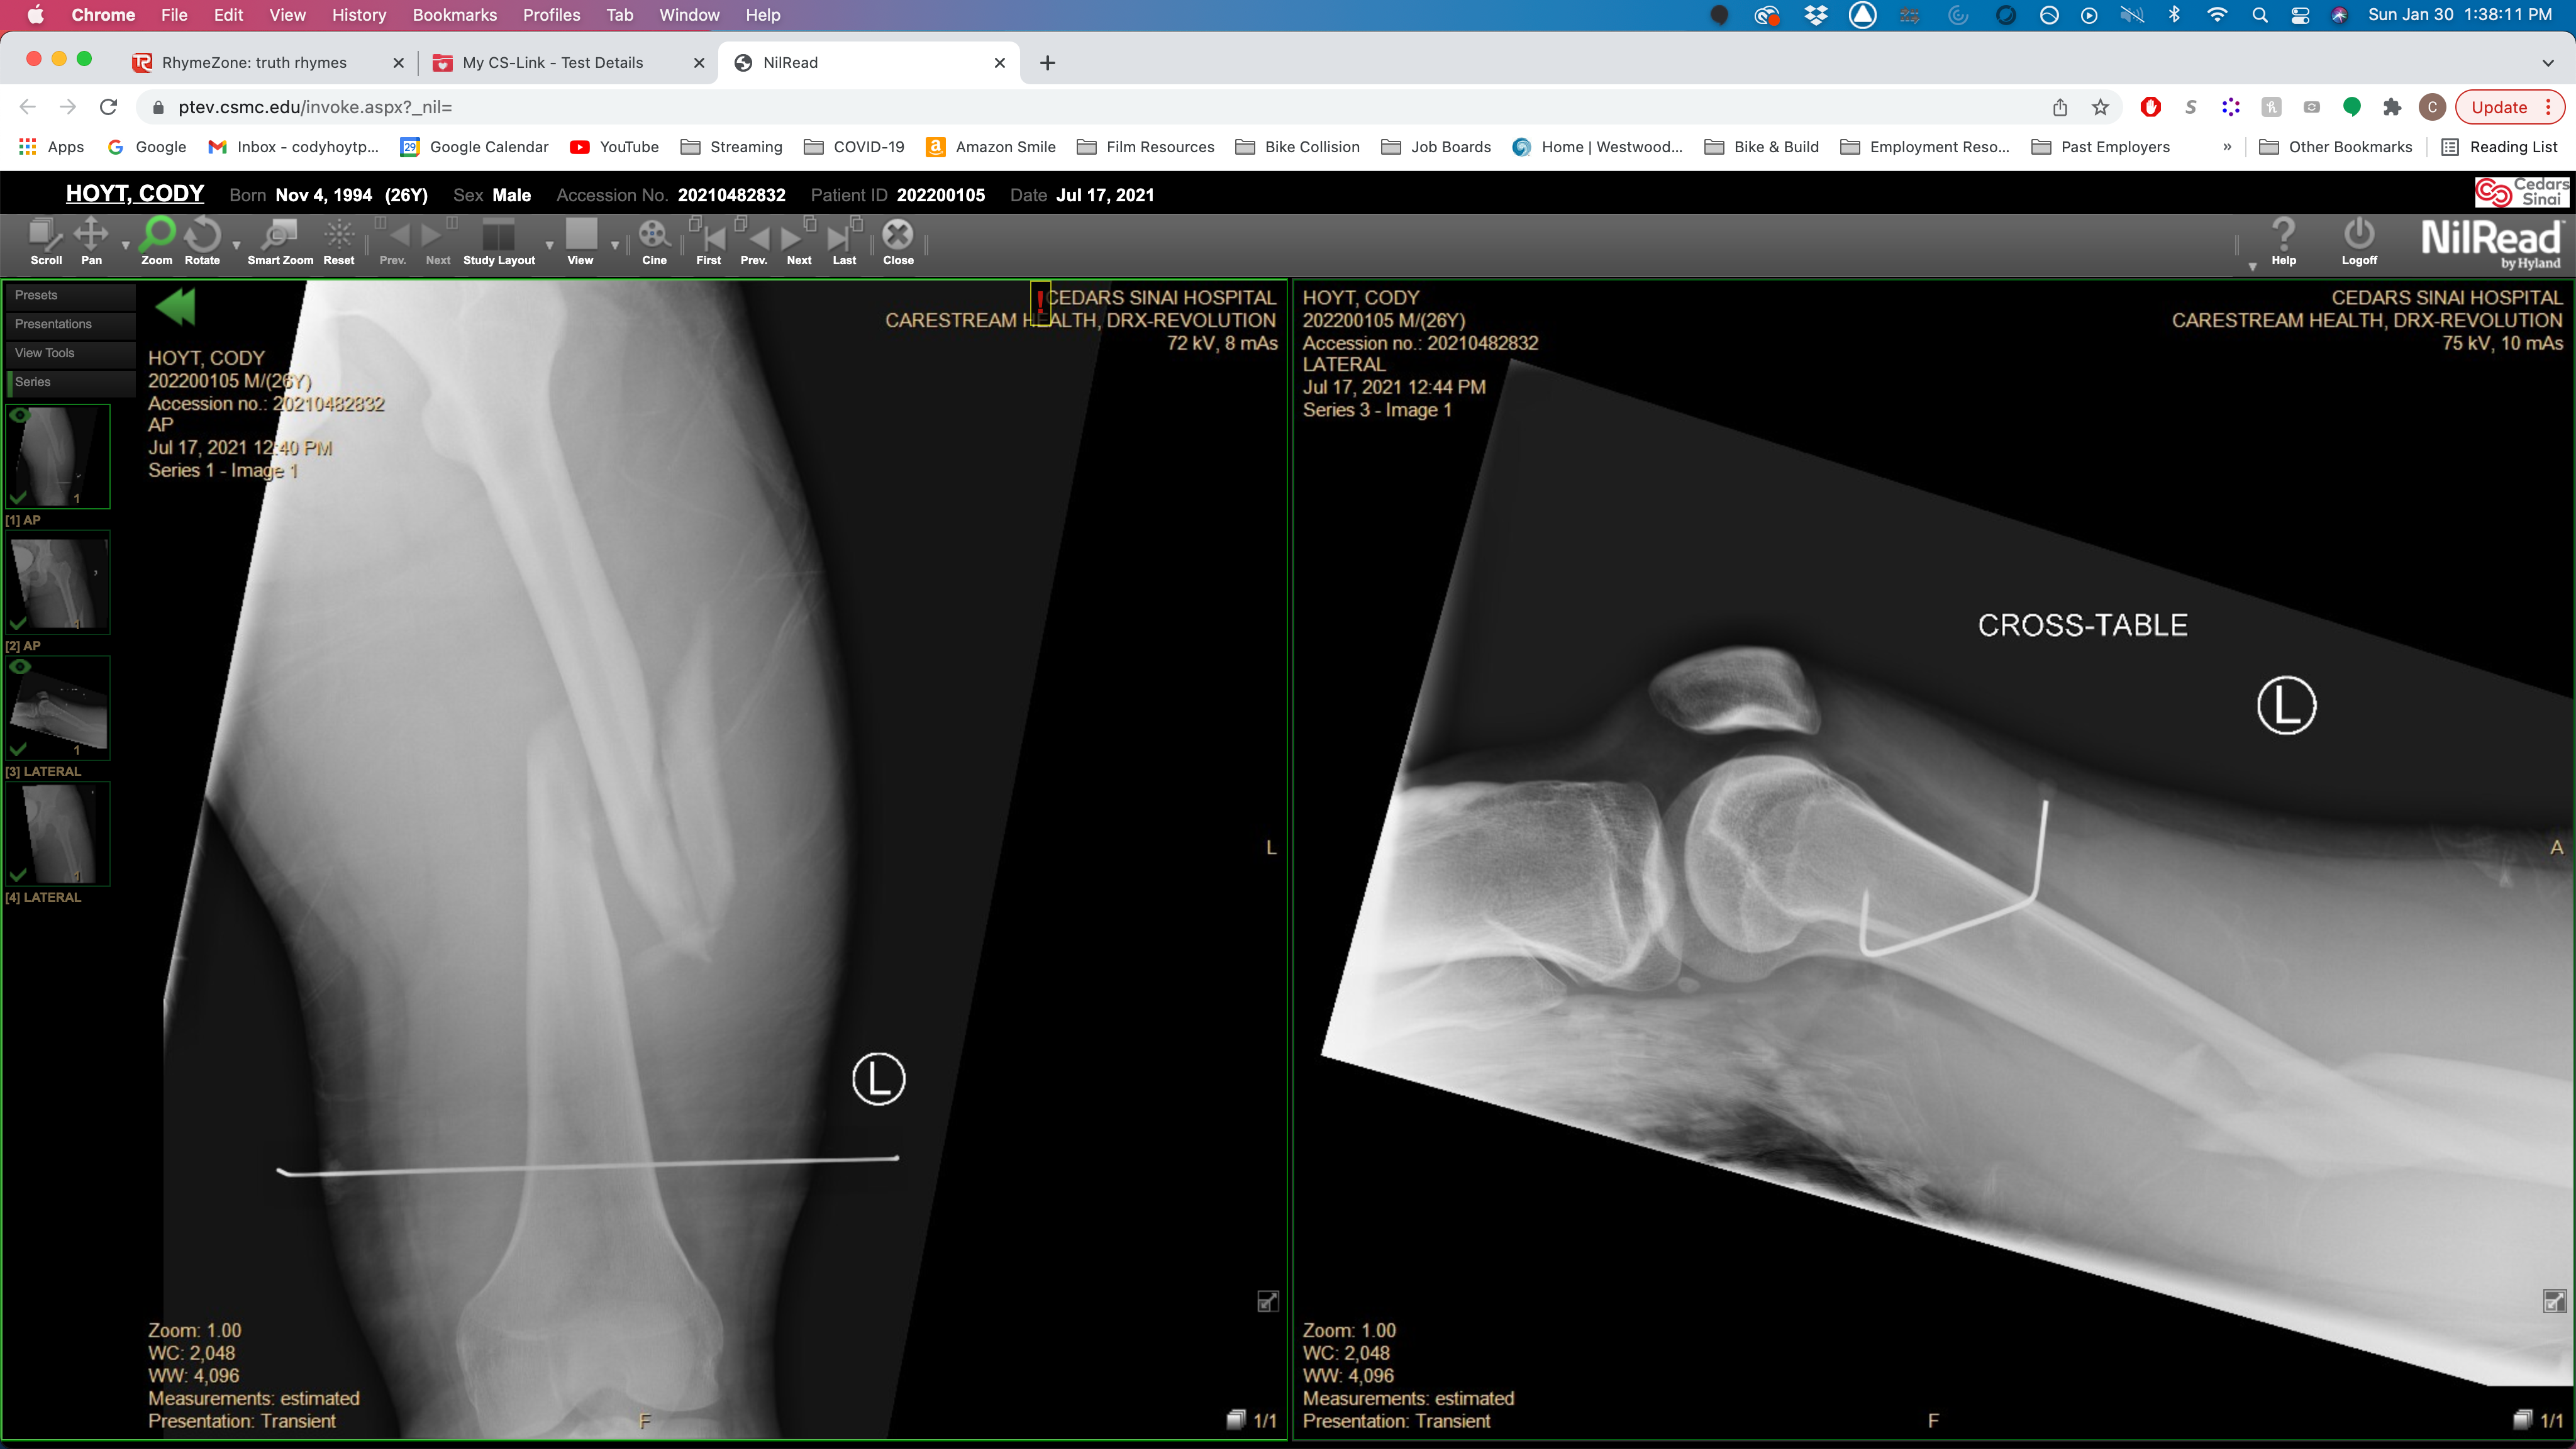

On July 17th, 2021 I was run over by a car while riding my bike in Los Angeles. I broke my left femur, left shoulder, and 10 ribs; punctured both lungs; and sustained 3rd degree burns.